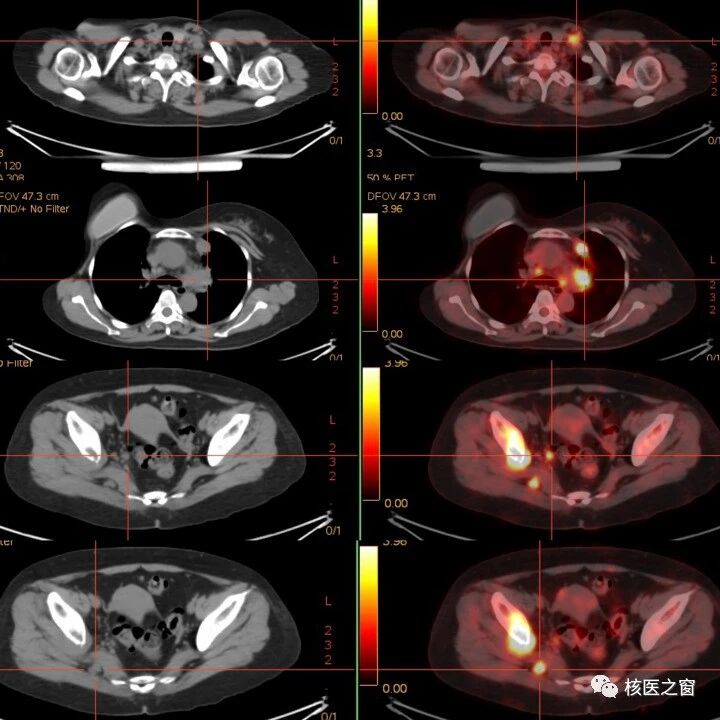

肿瘤术后,为什么还需要进行PET/CT检查?

PET-CT辐射到底有多大?常规体检中到底要不要做?